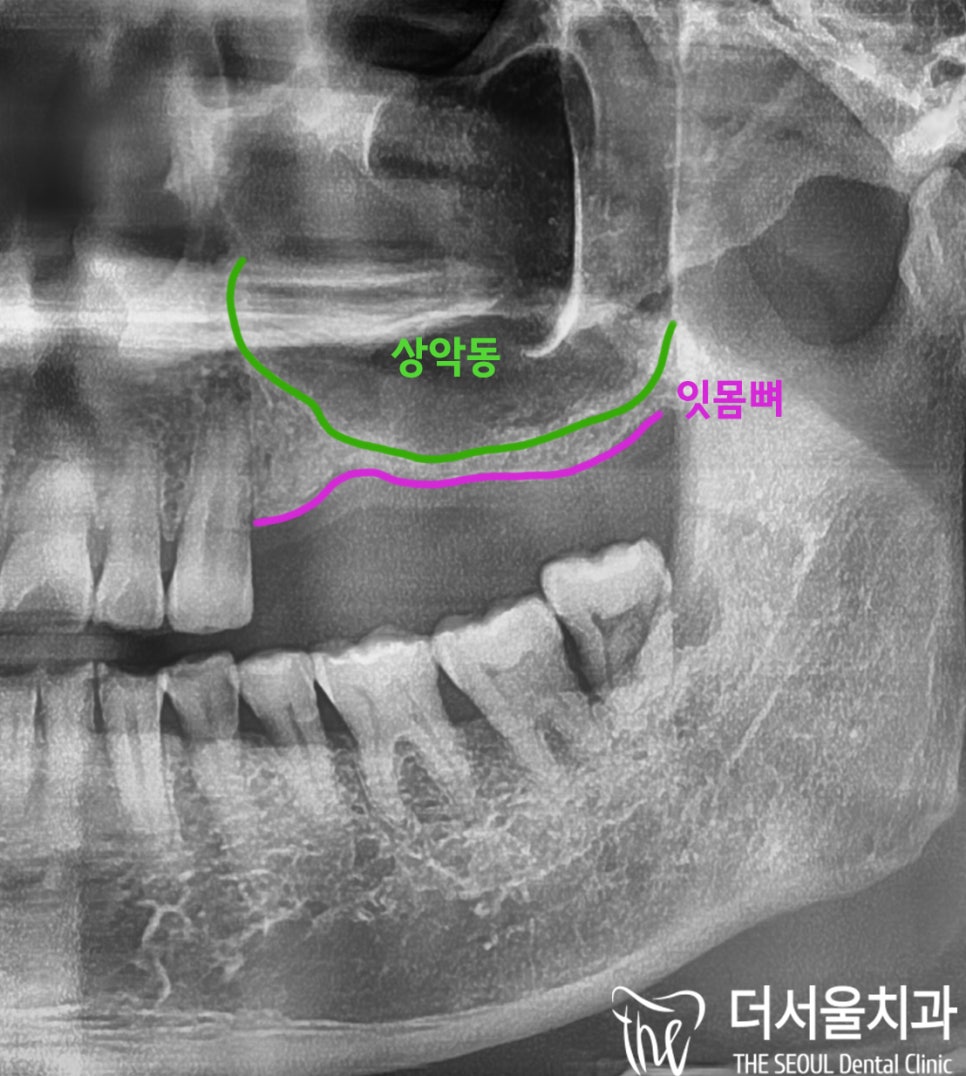

발치 후)

잇몸뼈가 얼마나 차올랐는지

확인해 봤는데

얼마 되지 않았습니다.

안 그래도

오랜 기간 치료받지 않고 방치해서

잇몸뼈가 없었는데

생각보다

많이 차오르지 않아서

뼈이식이 필요한 상황이었습니다.

더군다나

공기주머니 컸기 때문에

상악동 거상술 후 진행하기로 했습니다.

위턱은

아래턱에 비해서 두께가 얇고

상악동 이라는 구조물이 존재하고 있습니다.

지금처럼

잇몸뼈가 얼마 되지 않는 경우

상악동이라는 막을 들어 올리는 수술 을 하게 되는데

이를 ‘상악동 거상술’ 이라고 부릅니다.